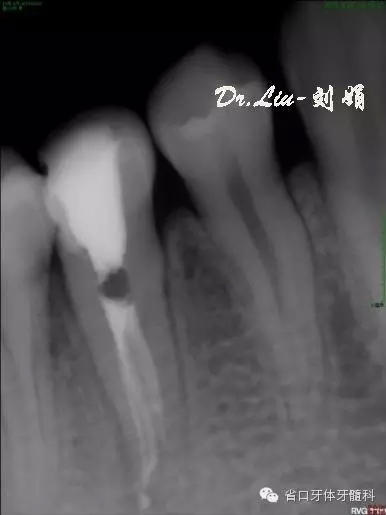

45橡皮障隔離下去封藥,清理根管,沖洗,紙尖干燥根管,拍攝試主尖片,顯微鏡下行熱牙膠根管充填,X線片顯示恰填。

圖9:試主尖

圖10:根充后X線片